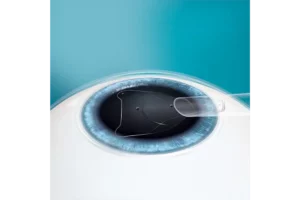

- EVO wordt direct achter de iris en vóór de natuurlijke kristallijne lens geplaatst.

- De toevoeging van de centrale aqua port bij EVO vergemakkelijkt de stroom van aqueous humor doorheen de lens.

- De EVO ICL-procedure vereist geen verwijdering van corneaweefsel.

- Geen preoperatieve perifere iridotomie vereist (PI’s)